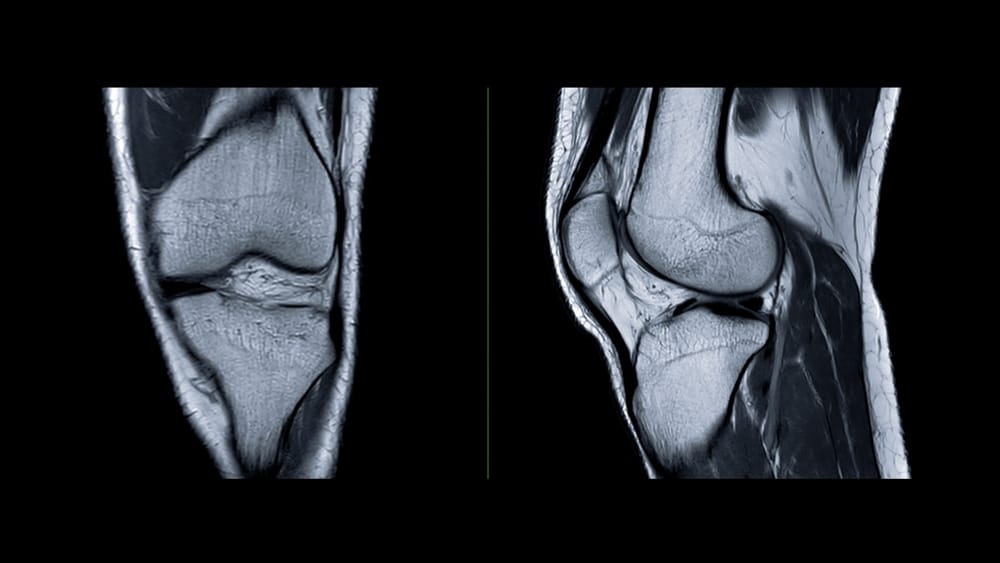

Diagnosing Your Knee Ligament Injury